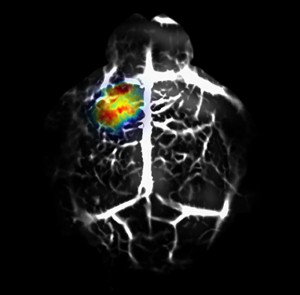

A team of engineers, led by Washington University’s Lihong Wang and postdoctoral researcher Junjie Yao, found that by genetically modifying glioblastoma cancer cells to express BphP1 protein, derived from a bacterium commonly found in soil and water, they could clearly see tiny amounts of live cancer cells as deep as 1 centimeter in tissue using photoacoustic tomography.